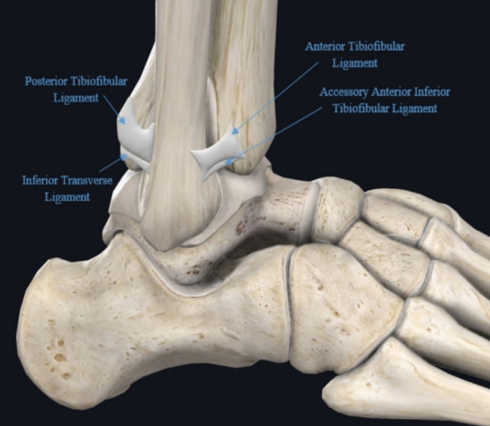

踝关节是胫腓骨远端形成的踝穴,并通过内、外侧两组韧带与距骨构成,下胫腓韧带复合体是踝穴的重要组成结构,连接胫腓骨,在解剖结构和维持功能方面起着重要作用。下胫腓联合包括胫腓骨远端和下胫腓联合韧带复合体。下胫腓联合韧带复合体由四条韧带组成,包括下胫腓前韧带、下胫腓后韧带、下胫腓横韧带和骨间韧带。在组成下胫腓联合复合体的诸韧带中下胫腓横韧带是最长的韧带,最宽的韧带是下胫腓骨间韧带,最厚的是下胫腓后韧带。下胫腓关节是一个微动关节,生理状态时可随着踝关节运动而出现旋转和平移的复合运动,包括上下、前后、旋转及侧方运动。踝关节骨折合并下胫腓联合损伤通常发生在旋前外旋、旋后外旋和旋前外展型损伤,其中以旋前外旋伴有下胫腓损伤最为常见。